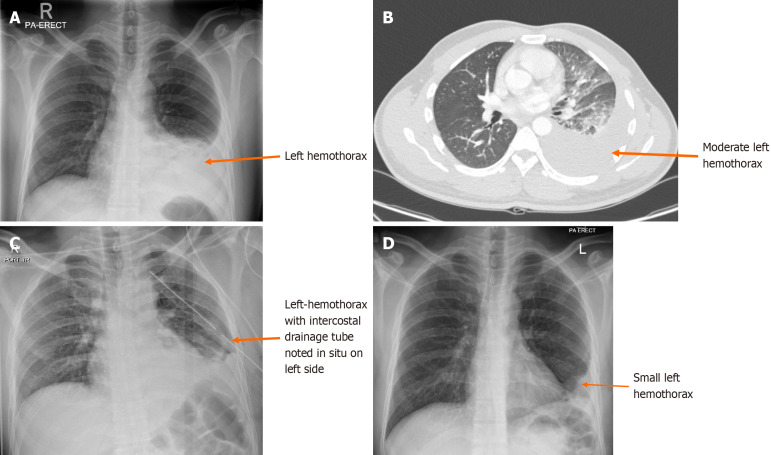

Methods: A retrospective observational study was conducted at Hamad General Hospital, Qatar, from June 2014 to October 2019, including all patients with hemothorax diagnosed via computed tomography (CT) following chest trauma. Based on the initial imaging study, the hemothorax was divided into right, left, and bilateral.

Conclusion: This study showed that a subset of patients continued to experience retained hemothorax despite early tube thoracostomy. Patients with a larger hemothorax, particularly on the left side, showed prolonged resolution times. Regular imaging such as CXR or CT is recommended for up to 14 days post-intervention. After this period, outpatient follow-up is generally safe, although some patients may still have a persistent hemothorax beyond two weeks.